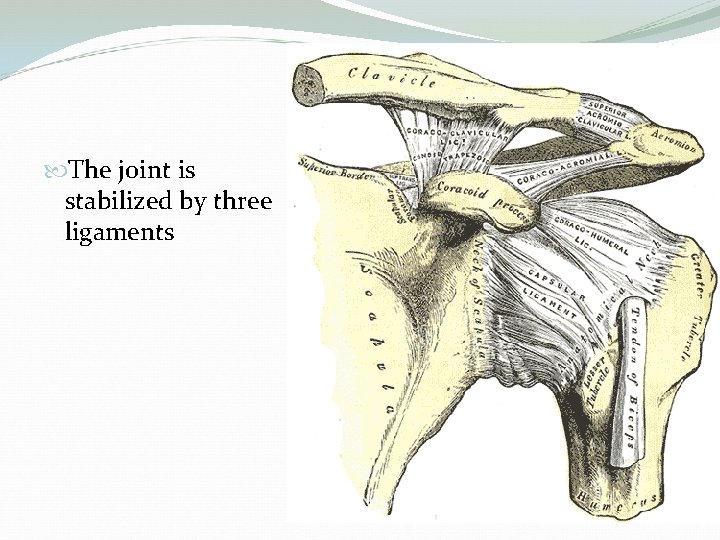

The joint is stabilized by three ligaments